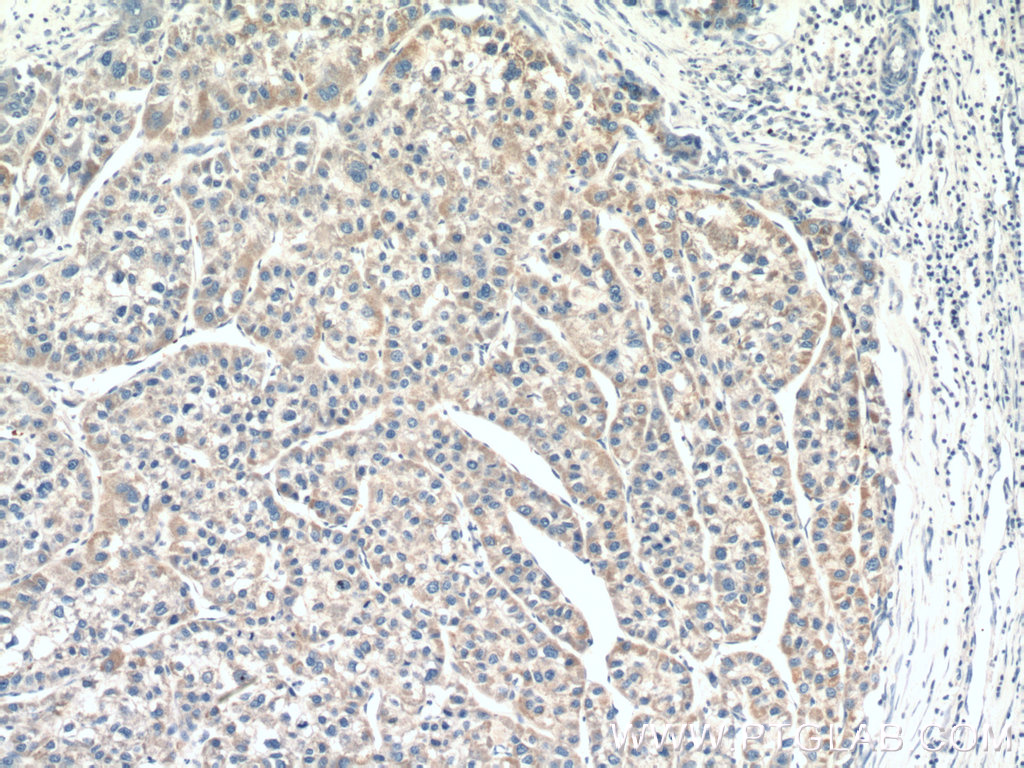

| Positive IHC detected in | human liver cancer tissue, human heart tissue Note: suggested antigen retrieval with TE buffer pH 9.0; (*) Alternatively, antigen retrieval may be performed with citrate buffer pH 6.0 |

| Immunohistochemistry (IHC) | IHC : 1:50-1:500 |